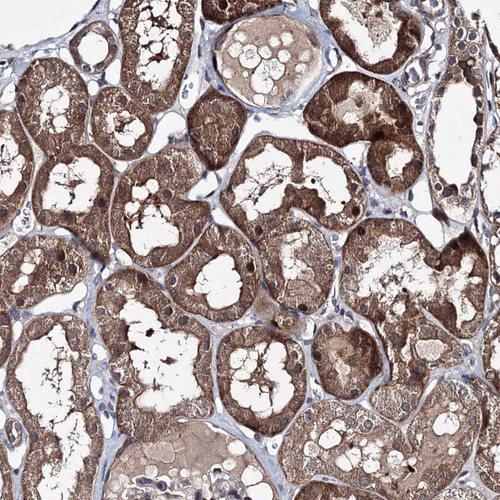

Immunohistochemical staining of human cerebral cortex shows moderate cytoplasmic positivity in neurons.